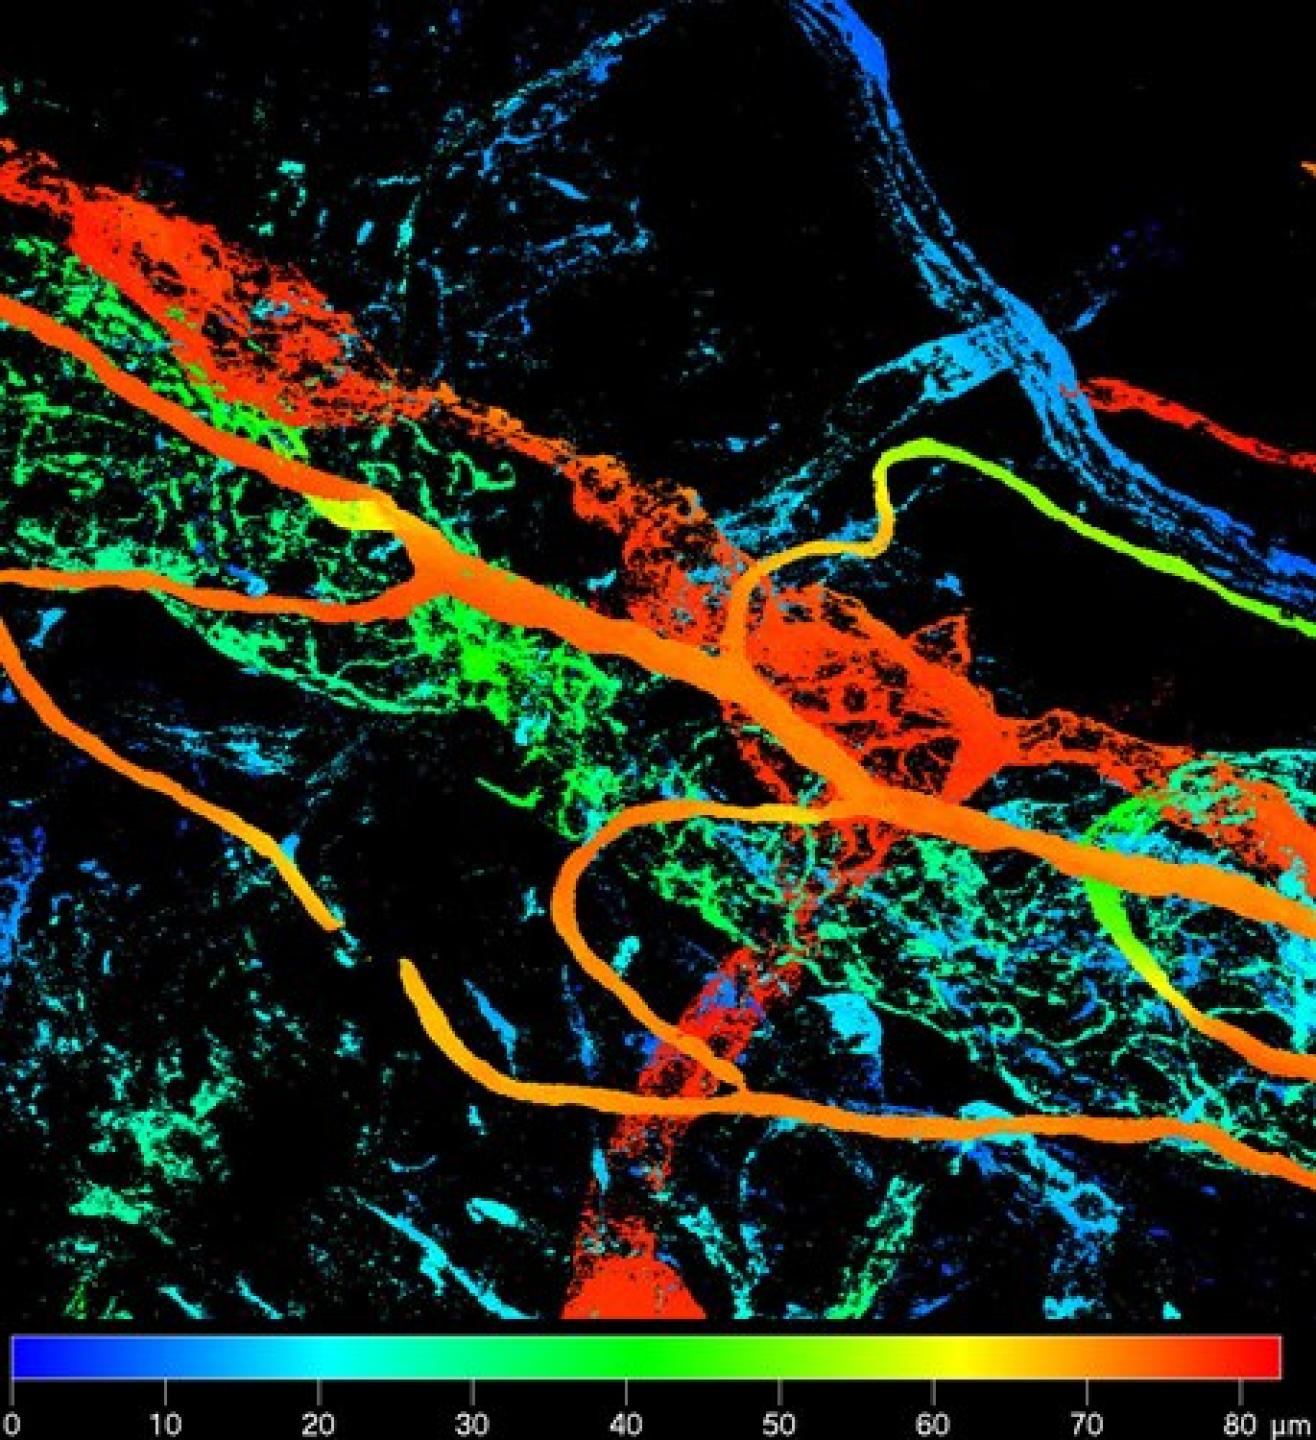

Depth-coded false colour projection of immunolabelled blood vessels in the anterior segment of the eye.

Depth-coded false colour projection of immunolabelled blood vessels in the anterior segment of the eye.